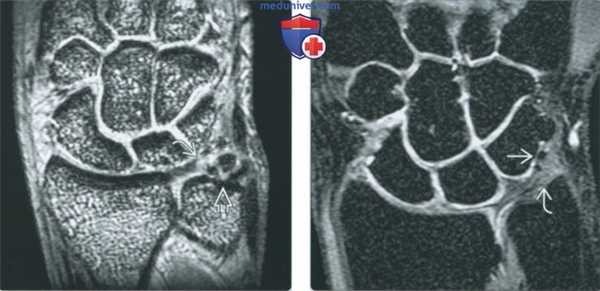

(Слева) МР-артрография в режиме Т1ВИ, коронарный срез, пациент, перенесший разрыв ладьевидно-полулунной связки: визуализируется дефект хряща в области ладьевидно-полулунного сочленения. Следует отметить, что истончение хряща на вогнутой поверхности головчатой кости не является патологией.

(Справа) МР-артрография в режиме Т2ВИ FS, коронарный срез, этот же пациент: отмечается отек костного мозга, обусловленный либо избыточной нагрузкой, либо патологическим движением. В то же время под относительно тонким нормальным хрящом головчатой кости отек костного мозга отсутствует.